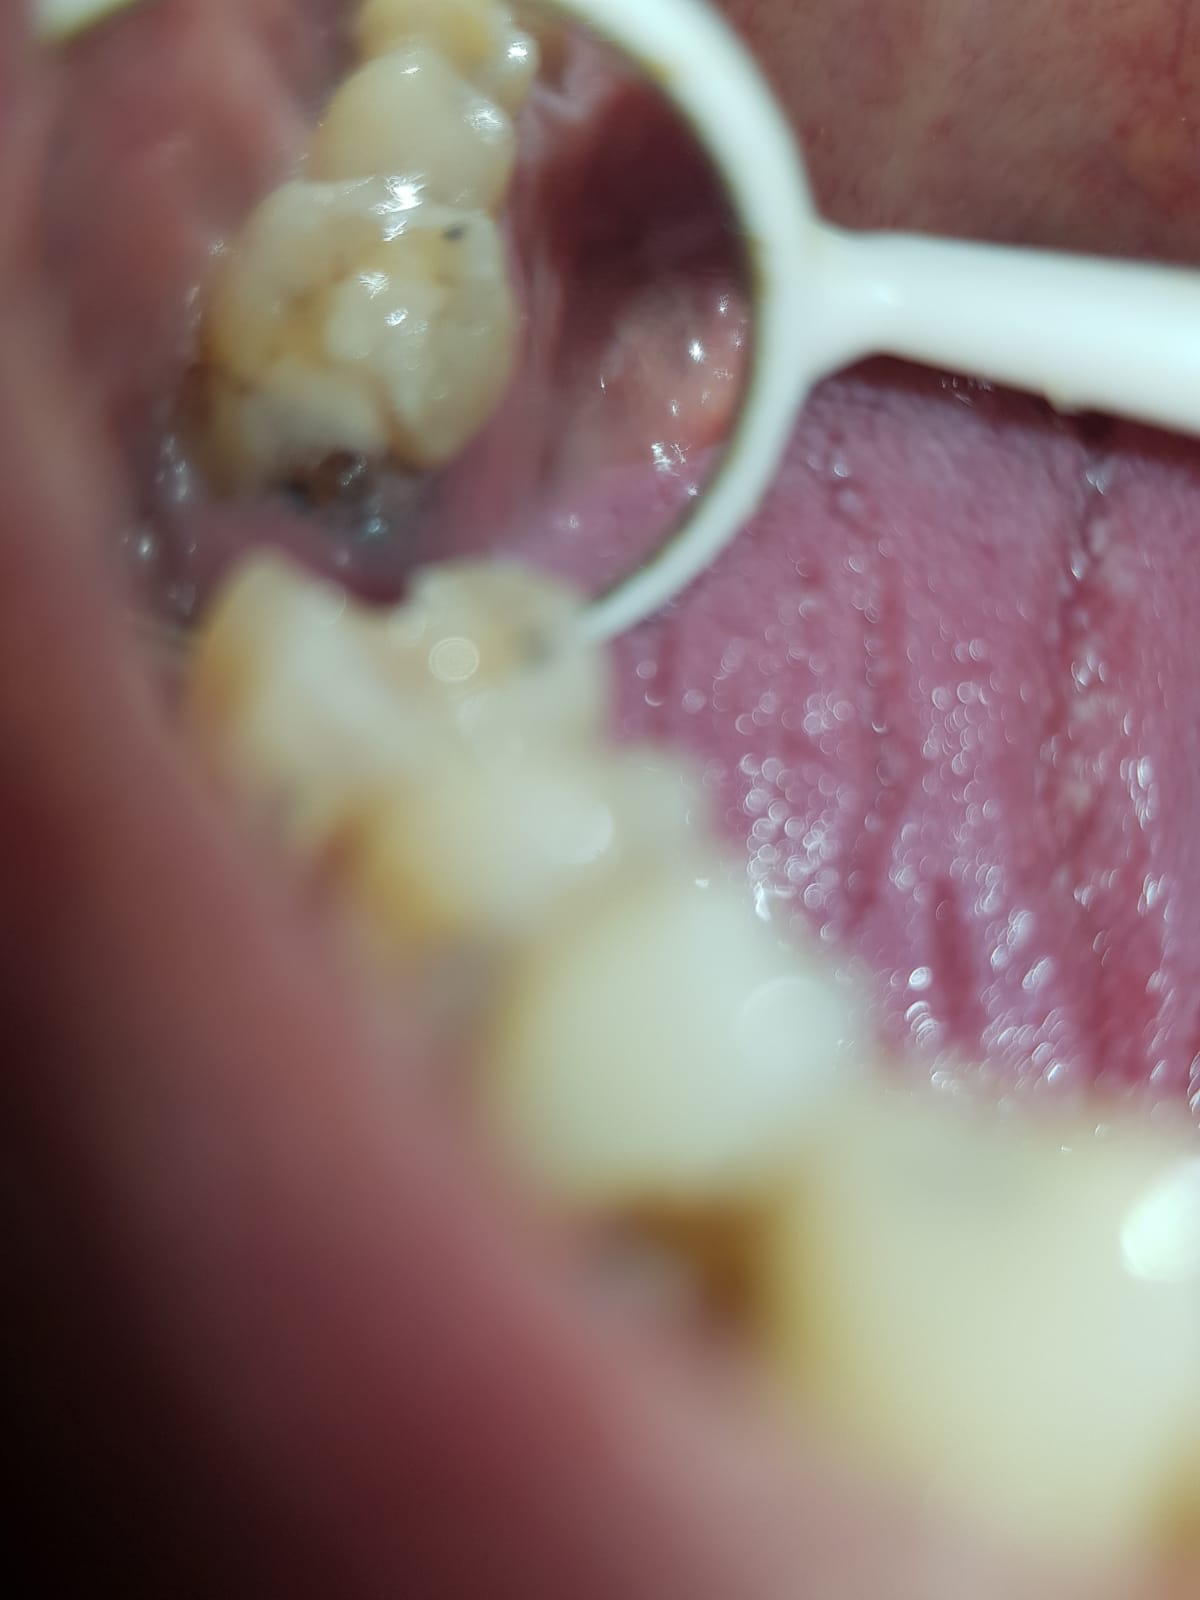

bij mij is een kies gebroken tot op het tandvlees en het is zwart van binnen. zou dit nog te redden zijn met een kroon of is het bederf dan al te ver gevorderd ? zie ook de foto

Attach